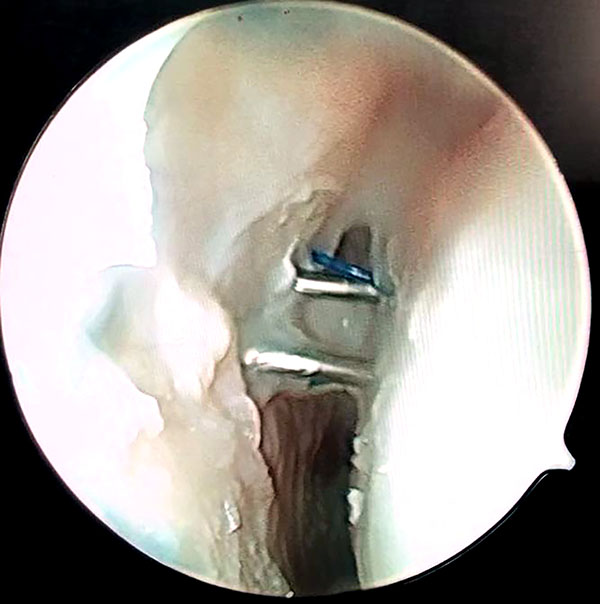

Se realiza visión por portal 6r y se pasa la aguja por la cápsula y uno de los sectores dañados del ligamento escafolunar hacia la articulación mediocarpiana donde se rescata la sutura y se retira por el portal MCR con visión MCU. Se repite este paso con otra aguja paralela a la primera que atraviese la cápsula y la otra parte del ligamento escafolunar dañada, y se rescata la sutura por articulación medio carpiana. Las 2 suturas rescatadas por mediocarpiano se anudan de forma simple, y se realiza el deslizamiento de los extremos de las suturas proximales con visión MCU, consiguiendo que el nudo quede anclado por mediocarpiano en el lig. Escafolunar (figs. 5 a 10).

Figuras 1 a 10: Muestran el ingreso de las agujas desde el portal radiocarpiano al mediocarpiano y el retiro de los hilos por el portal MCR con el nudo anclado en espacio mediocarpiano.